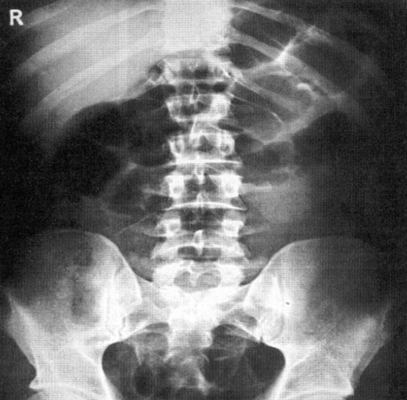

Рис. 541. Обзорный снимок живота, выполненный в положении больного на спине.

Проникающее огнестрельное ранение брюшной полости. Хорошо видны жидкость в боковых каналах живота (стрелки), свободная кровь в брюшной полости (двойные стрелки) и металлические инородные тела (тройные стрелки).